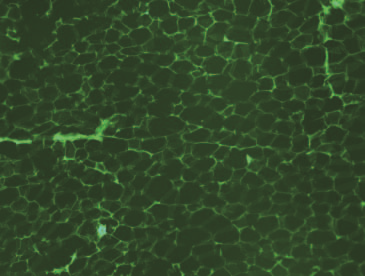

肝脏

胰腺

心脏

肺部

肌肉

脂肪组织